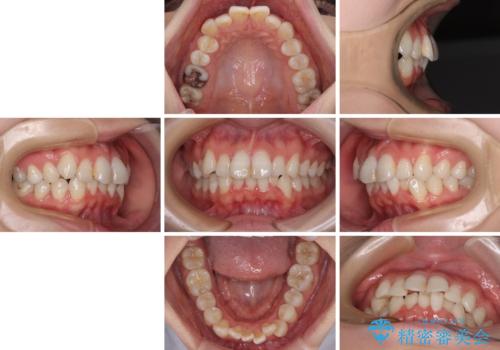

- 上下前歯のデコボコを改善したいとのことで来院された患者様です。

マウスピースを長時間装着し続ける自信はあまりないとのことでしたが、目立たない装置であれば頑張って装着するとのことで、インビザラインによる矯正治療を行うこととしました。

初めの1年くらいは何とか頑張って装着してくださいましたが、途中から変化をあまり感じられなくなり、日々の装着時間は徐々に短くなってしまいました。

前歯のデコボコはもっと改善できましたが、3年半が経過し、初診時と比べたら大幅に良くなったとのことで終了することとなりました。